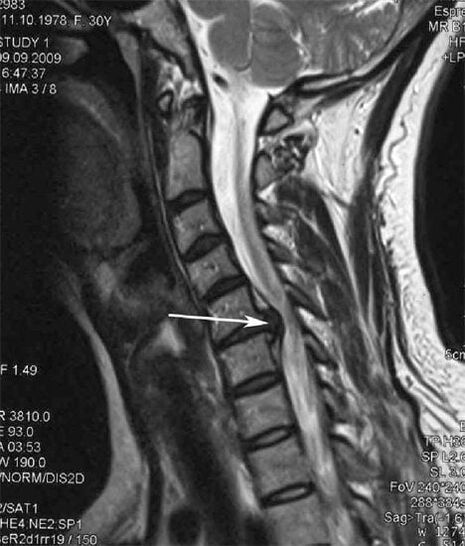

In the initial stages, osteochondrosis is detected using mri.The pathology can then be diagnosed using X-rays.In the X-ray of the cervical spine, a decrease in the distance between the vertebrae, pathological changes in the facet joints and osteophytosis are noticeable.

Many people complain that they cannot turn their neck due to the severe pain that appears after suddenly lifting something heavy.This phenomenon indicates the formation of a herniated disc.The cause of pain in the back, neck and upper extremity is pinching of one of the nerve roots originating from the spinal cord.

| Cervical osteochondrosis | The appearance of pathological changes in one or more spinal movement segments.Spinal mobility, development of myofascial pain syndromes and pinching of spinal roots | Cervical pain, paresthesia, and motor disorders spreading to the back of the head and upper limbs.Detection of characteristic changes in the spine in MRI and X-rays |